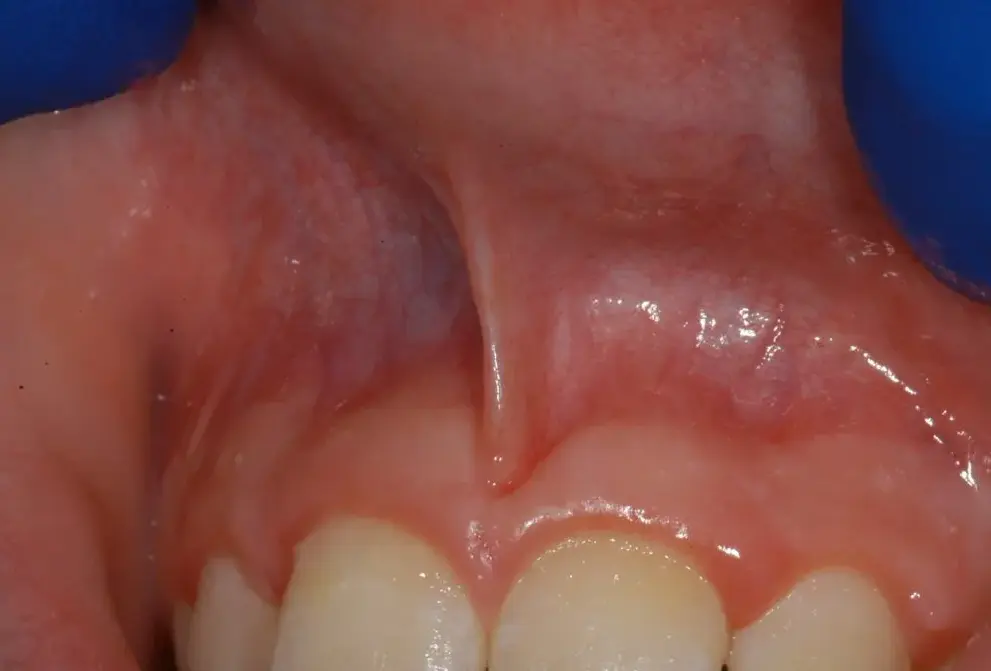

El frenillo labial es un tejido conectivo fibroso que une la encía con el labio superior o inferior. Todos tenemos dos frenillos labiales: uno superior y otro inferior, siendo el superior generalmente más grueso y a veces motivo de preocupación cuando su desarrollo no es el adecuado.

Desde la infancia, el frenillo labial puede presentar un desarrollo anómalo, manifestándose como un frenillo hipertrófico o de inserción baja. Esto puede provocar un espacio interdental mayor al normal, conocido como diastema, y afectar tanto la estética dental como la funcionalidad bucal.

Las principales señales de que algo no va bien con el frenillo labial incluyen: